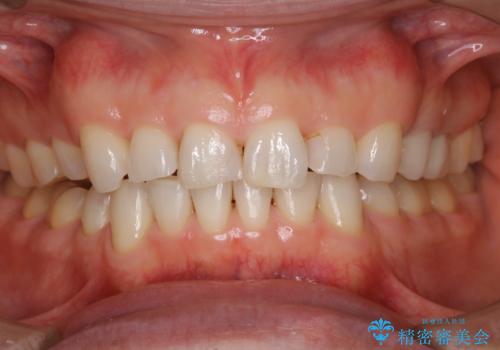

一か所茶色く色が残っている所がありますが、これは詰め物の変色です。

以前にCR(コンポジットレジン)による虫歯の治療での充填がされています。

CRは経年的に劣化や変色、着色がついてしまいます。

PMTCでしっかりとクリーニングを行うと、古いCRが目立つことがあり、気になる際は詰め替えを行います。